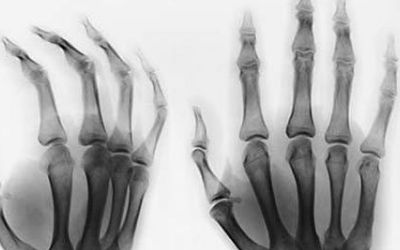

类风湿性关节炎是最常见的风湿性关节炎之一,全国有500多万患者。是病因不明的慢性、以炎性滑膜炎为主的系统性疾病。临床表现为手、足小关节多关节、对称性、侵袭性关节炎症,常伴心、肾、肝等器官受累。与风湿性关节炎不同,该病可导致关节畸形和功能丧失。

类风湿性关节炎的治疗以药物治疗为主,除了固醇抗炎药、传统慢作用抗风湿药等基础治疗外,还可以使用生物制剂和中药联合治疗。类风湿性关节炎晚期容易发生关节畸形。